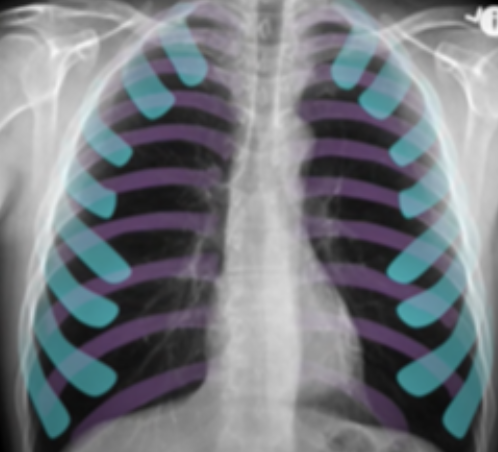

what ribs should you see on a chest xray?

A

-5-6 anterior ribs (in blue in pic)

-9 posterior ribs (purple)

what condition might be present if there’s more than 6 anterior ribs visible on xray?

-COPD